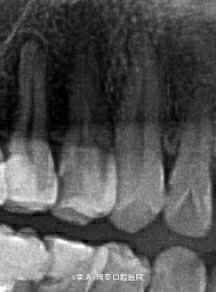

右上后牙龋坏,咬合不适1年

14深龋,探及穿髓孔 15根尖暗影,牙髓活力丧失